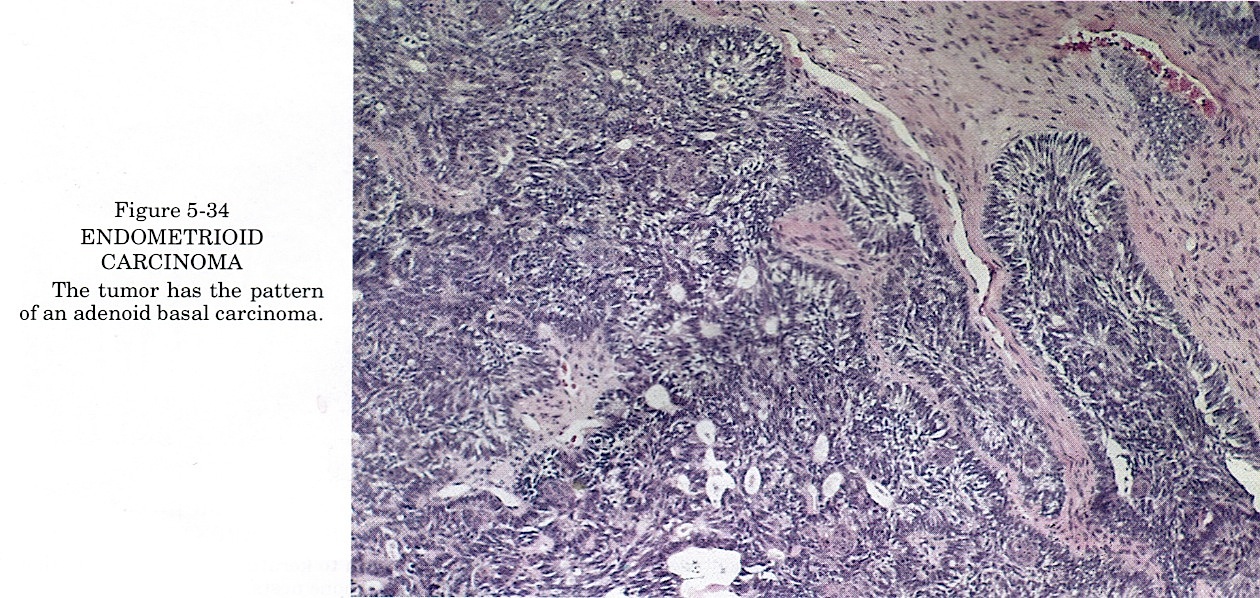

Карнификация Легкого: Микропрепараты и Диагностика

Раздел: Калейдоскоп образов